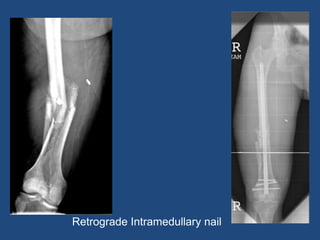

Retrograde Intramedullary nail

Femoral Intramedullary Nailing •Antegrade (Through hip) • Common, and can be used for all shaft fractures • Starting point options • Retrograde (Through knee) • Do not need fracture table • Bilateral femur fractures • Floating knee • Distal fracture